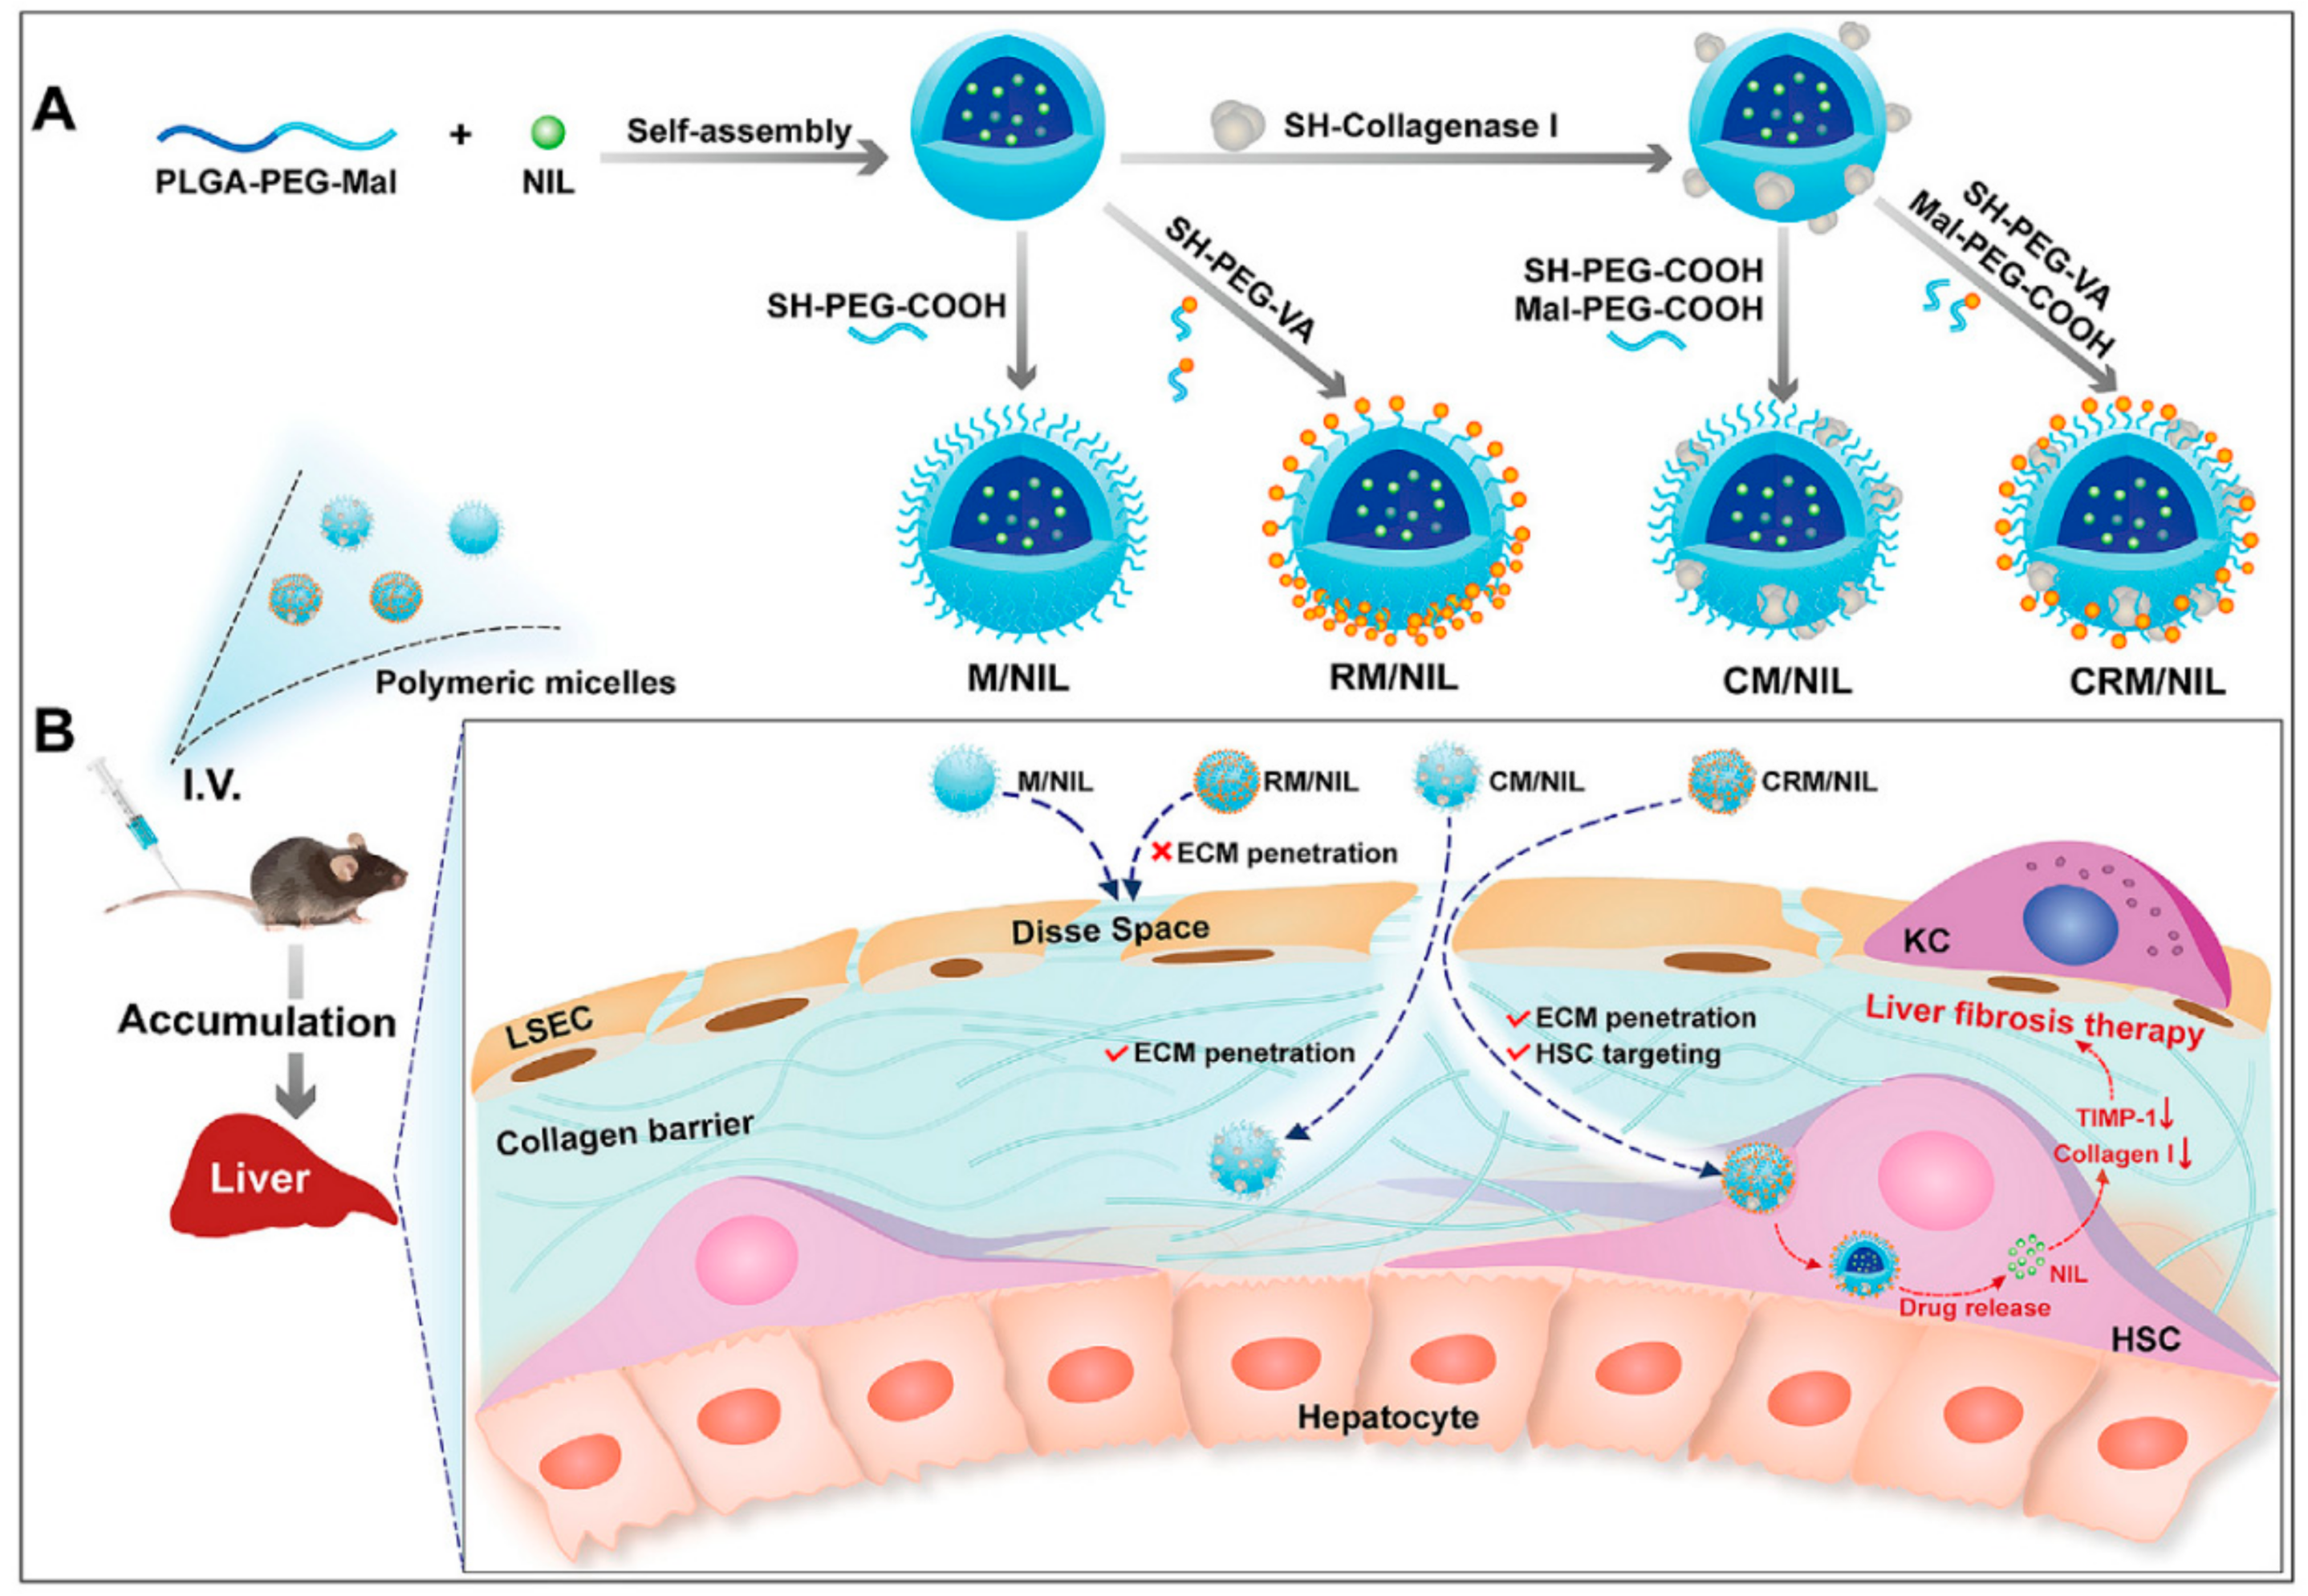

4.3. NPs as Drug Carriers with Targeting Ligands for the Treatment of Liver Fibrosis